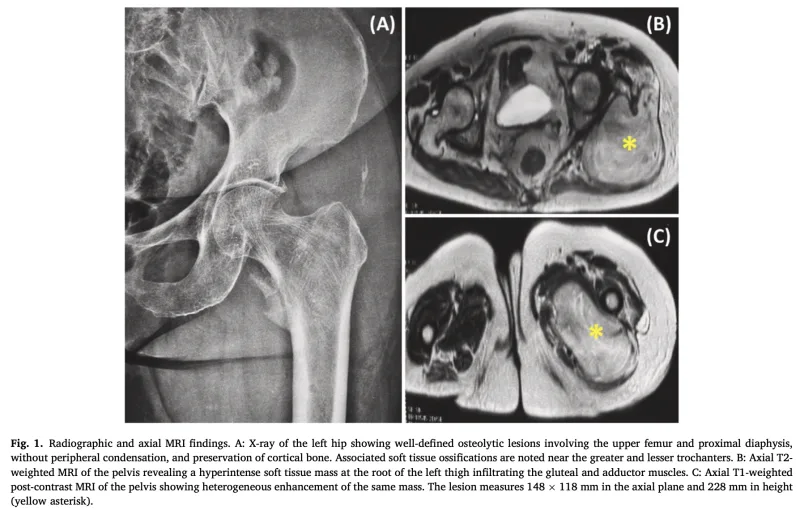

新規患者さんのうちの一人は, 造影MRIの結果, 軟部腫瘍と診断し, 生検が必要でした.

しかし, 他院の血液内科で多発性骨髄腫の治療中だったため, 病状照会を行ってから, 予定することにしました.

多発性骨髄腫は, 骨に生じる悪性腫瘍です.

通常, 骨の中(骨髄)に病変を形成しましすが, 15 %程度の患者さんでは, 骨以外の部位にも病変を生じることがあり, まれに筋肉の中にも腫瘍を形成することがあります.

それに該当するのかどうか, 今後検査で明らかにする必要があります.